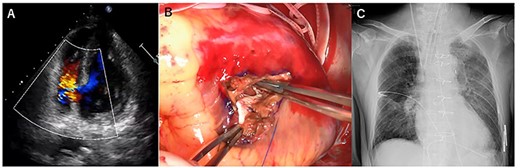

A few hours after treatment, his blood pressure collapsed despite the use of high-dose inotropic support and IABP. On cardiac auscultation, a holosystolic murmur had clearly developed at the left lower sternal border. Since transthoracic echocardiography showed VSP with a left-to-right shunt (Fig. 2A and B), VA-ECMO was started in the ICU and then the patient was transferred to the operating room (OR). Through the median sternotomy, cardiopulmonary bypass was established with aortic and bicaval cannulations, and cardiac arrest was induced with antegrade cold blood cardioplegia. The ventricular septum was approached through the right ventricle parallel to the right posterior descending artery. The VSP was repaired with an extended sandwich patch described by Asai et al. [2] Simultaneous coronary artery bypass grafting to the LAD was also performed using a vein graft. VA-ECMO was removed in the OR, and the IABP was removed on postoperative day (POD) 7. His CHF clearly improved (Fig. 2C), and he was extubated on POD 8.

Transesophageal echocardiography showed a defect with a left-to-right shunt (A). Ventricular septal perforation (VSP) (B). Postoperative chest X-ray (C).